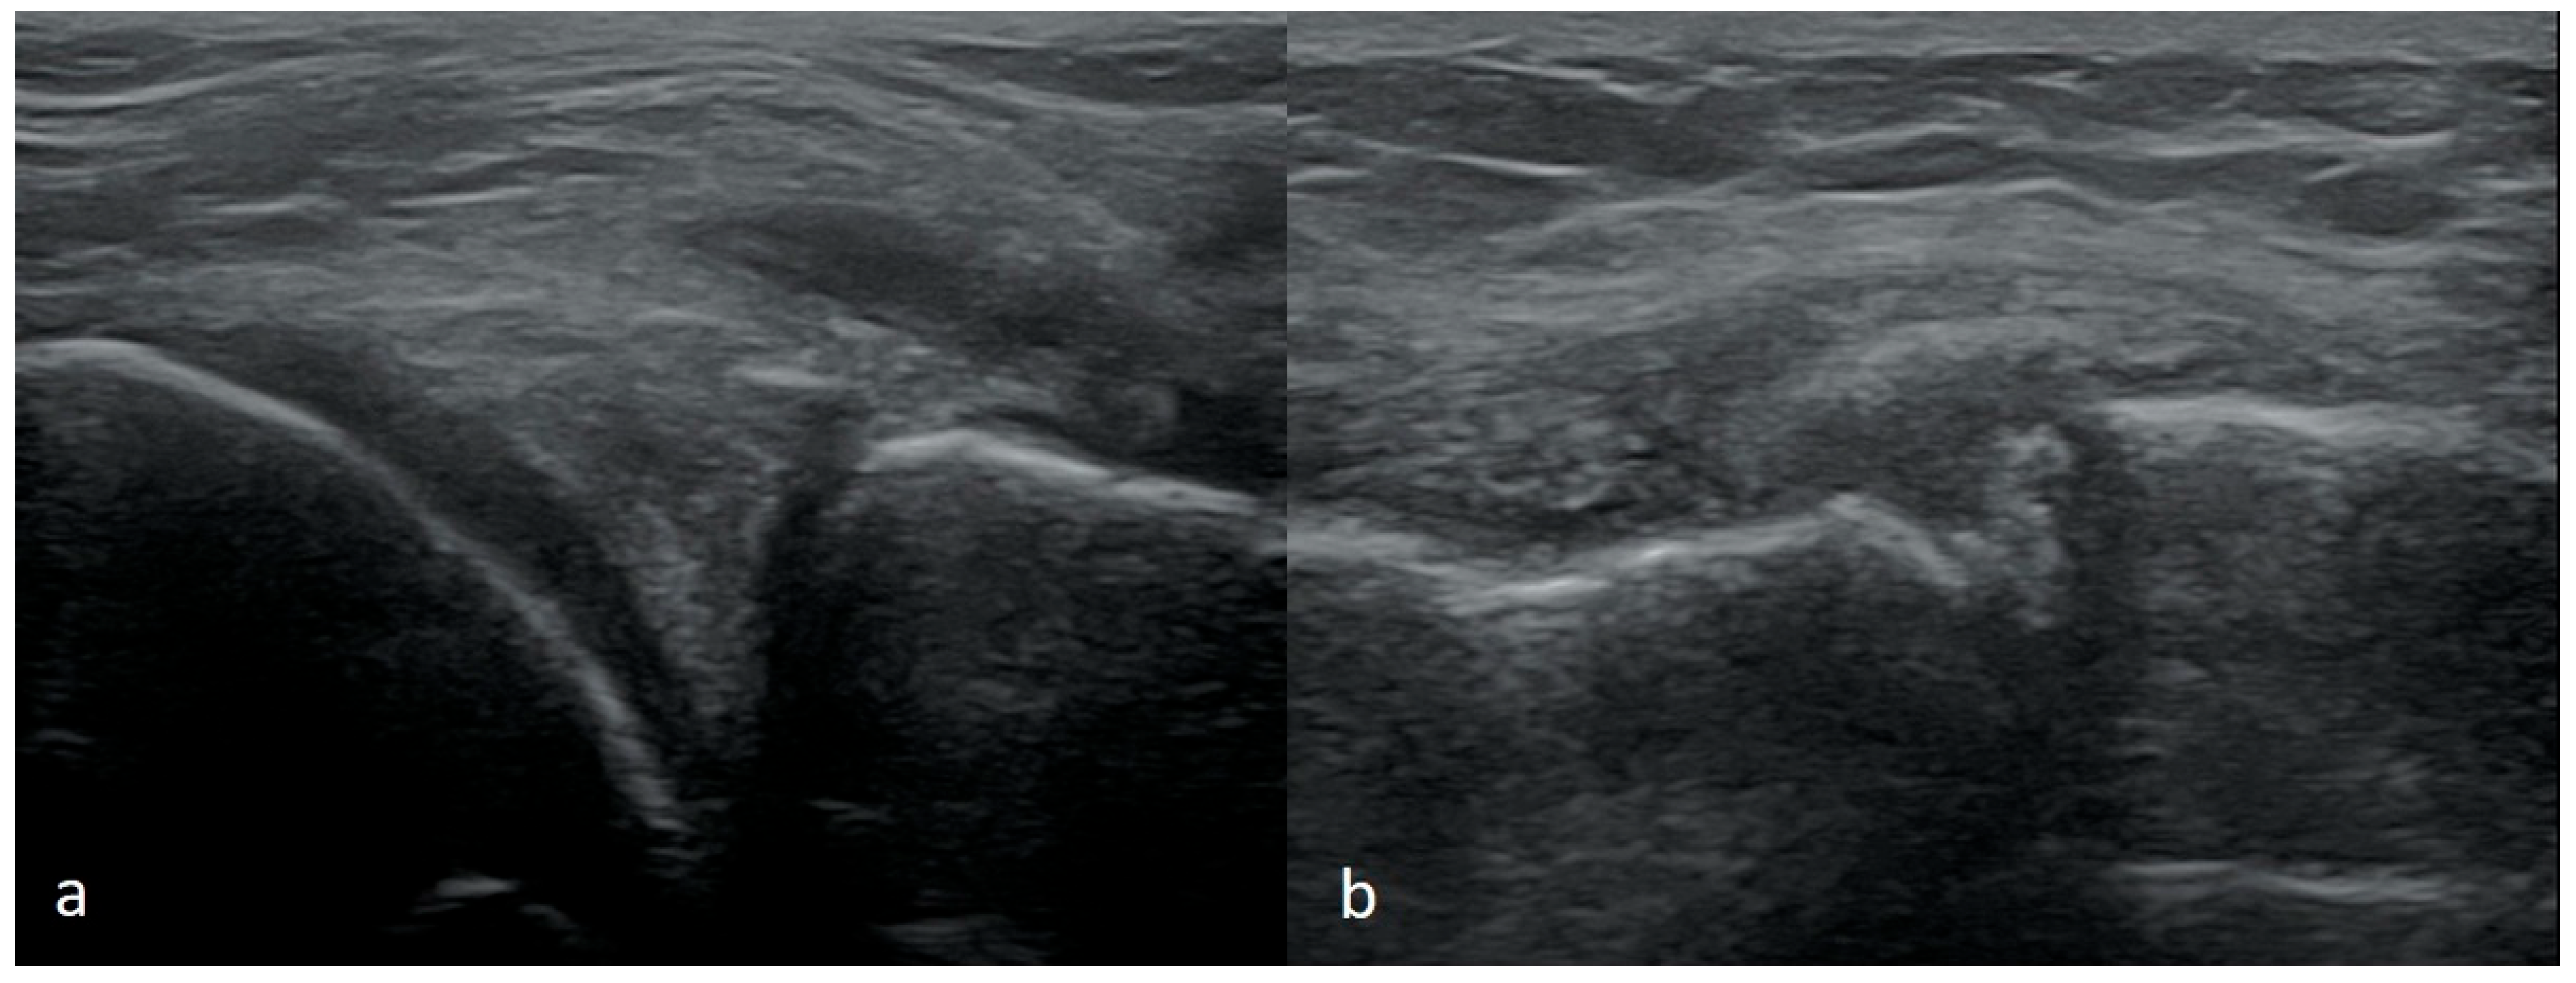

3.1.1. Meniscus Tears

3.1.2. Meniscus Cysts

3.1.3. Bucket-Handle Tears

3.1.4. Meniscal Flap Tears

3.1.5. Degenerative Changes of Menisci